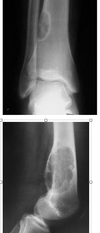

Describe this XRay? 15yo boy with painful mass. Differential? Top Diagnosis? Prognosis and Prognostic factors?

EWING SARCOMA

Differential

- ewing

- osteosarcoma

- less likely

- leukemia

- rhabdomyosarcoma

- neuroblastoma (<5yo)

16yo female with painful thigh. Top Diagnosis? How will she present to you? Radiographic findings typical of this?

Ewing Sarcoma

Presentation

- pain often accompanied by fever

- often mimics an infection

Physical exam

- swelling and local tenderness

Radiographs

- large destructive lesion in the diaphysis or metaphysis with a moth-eaten appearance

- Most common diaphyseal lesion

- Common in pelvis

- lesion may be purely lytic or have variable amounts of reactive new bone formation

- periosteal reaction may give “onion skin” or “sunburst” appearance

- Codman’s triangle

- associated soft tissue mass

12 yo male comes in with fever, and painful left hip. Below is his XR. Diagnosis? Managment? Treatment?

Ewing Sarcoma

Differential

- infection

- leukemia

- osteosarcoma

- neuroblastoma (if young)

Radiology

- permative, moth eatten appearance

- diffuse, aggressive, lytic lesion with periosteal reaction

- may be evidence of onion skinning or sunburst

- ill defined margins, associated soft tissue mass